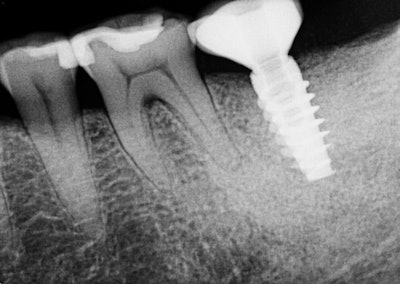

Oral exam revealed a lower left second molar tooth with class III mobility and severe occlusal wear. Periapical pathology was present because of a poorly treated root canal. A CBCT scan gave us a clear understanding that tooth #18 was hopeless and was literally floating in pathology.

This patient was a medical professional and was thankful for the level of expertise that we provided her, and she moved forward with the extraction, bone graft, implant, and restoration of tooth #18 that was necessary to return her to a full complement of teeth.